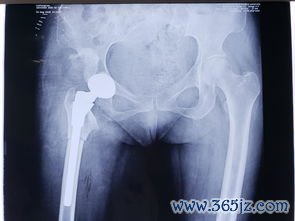

先天性髋关节脱位:髋关节不稳

先天性髋关节脱位:髋关节不稳的机制、表现与临床意义 先天性髋关节脱位(DDH)是儿童骨骼系统最常见的畸形之一,其本质是髋臼与股骨头之间的匹配关系异常,导致关节稳定性丧失。髋关节不稳并非一个孤立的症状,而是连接遗传易感性、宫内环境、产后力学因素与远期功能障碍的核心病理生理环节。深入剖析髋关节不稳,有助于我们更全面地理解DDH,并为临床实践提供清晰的指引。 一、...